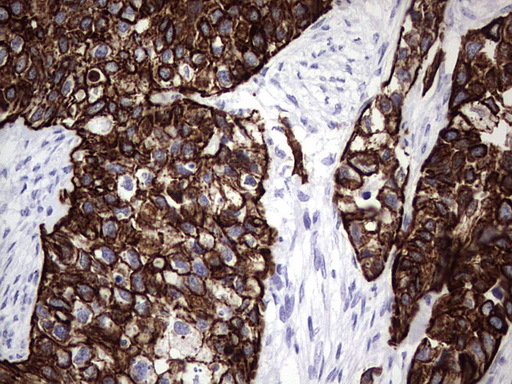

- IHC of paraffin-embedded Adenocarcinoma of Human breast tissue using anti-ENKUR mouse monoclonal antibody. (Heat-induced epitope retrieval by 1 mM EDTA in 10mM Tris, pH8.5, 120°C for 3min).